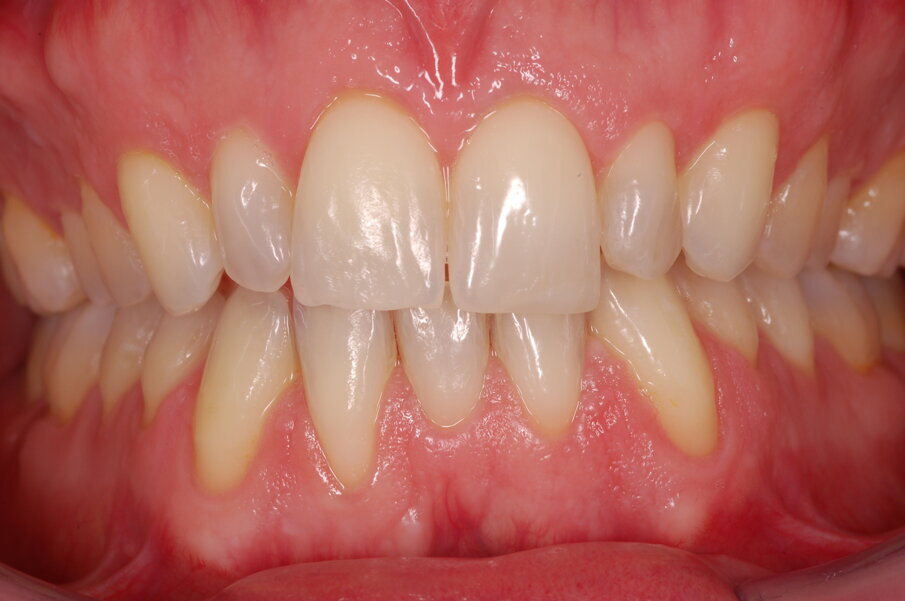

Diagnosi ed eziologia Un uomo sano di 39 anni si è presentato nel nostro studio ortodontico lamentando un aspetto dentale poco attraente e la paura della chirurgia ortognatica proposta da un altro ortodontista. Clinicamente, il profilo del paziente era rettilineo e la vista frontale non mostrava alcuna asimmetria facciale. L’esame funzionale non ha rivelato alcuna deviazione mandibolare o riduzione dei movimenti. Il paziente non aveva dolori articolari e non sono stati rilevati rumori articolari. Era presente una lieve occlusione molare bilaterale di Classe II, un morso aperto e un grave affollamento in entrambe le arcate. L’affollamento era particolarmente grave nell’arcata mandibolare, sebbene mancasse l’incisivo centrale mandibolare destro. Gli incisivi mascellari erano di piccole dimensioni, suggerendo una discrepanza dell’indice di Bolton se fossero stati presenti tutti e quattro gli incisivi mandibolari. Erano inoltre presenti un morso incrociato nella regione dell’incisivo laterale superiore sinistro e una grave rotazione distale del secondo premolare mandibolare sinistro (Figg. 1-8).

Figg. 1-8_Fotografie facciali e intraorali pre-trattamento.